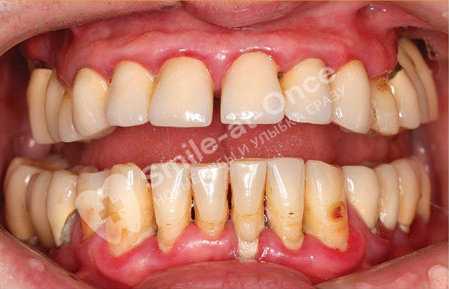

Глубина – 4-6 мм. Присутствует налет, твердый камень желтого, серого или коричневого цвета, расположенный в том числе глубоко под деснами – в области зубных корней.

Присутствует в пародонтальных карманах.

I стадии (реже – второй). Зубы смещаются в щечно-язычном, вестибуло-оральном и/или небно-дистальном направлении не более чем на 1 мм (вперед-назад и вправо-влево). То есть буквально разъезжаются по ряду, особенно если уже произошла потеря части из них. Возможно появление диастем и трем (щелей между зубами).

Происходит убыль костной ткани вплоть до 1/2 высоты зубного корня за счет разрушения (деструкции) межальвеолярных перегородок. Появляются очаги остеопороза – кость становится все менее плотной. Наблюдается достаточно ярко выраженная потеря ткани.